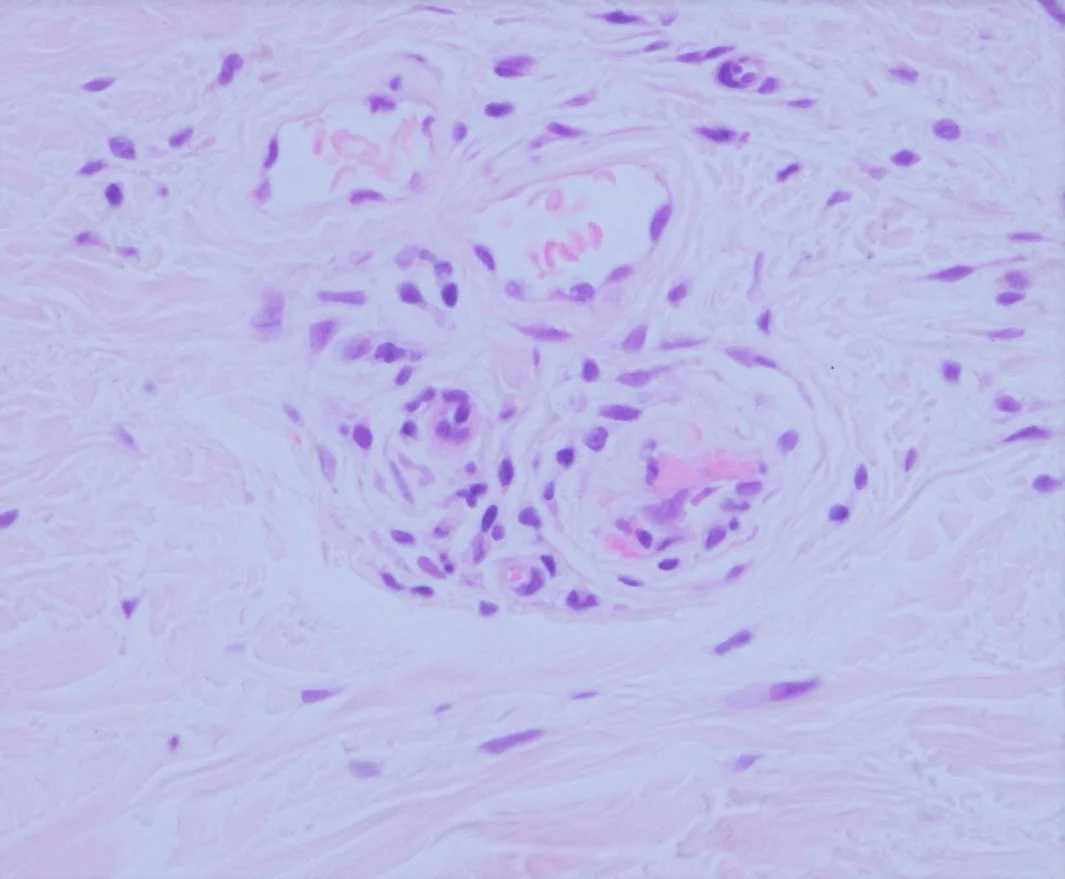

Clinical: 54yo male pigmented purpuric dermatosis